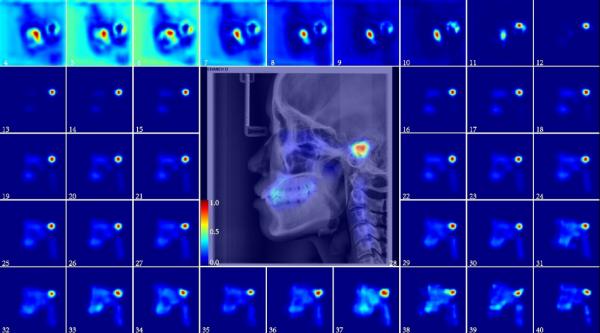

在现有研究基础上,西安交大口腔医院复杂专科张智勇医生基于正畸临床常用的头颅定位侧位片(LCR)的大样本数据集,通过年龄推断的深度学习模型提取年龄相关特征,用Grad-CAM方法生成各个年龄的衰老显著性图,以显示不同年龄头颅区域各组织和年龄的相关性及相关强度,生成年龄相关动态注意(ageing-related dynamic attention)图。实验结果表明,年龄相关动态注意随年龄的变化具有动态变化规律。

衰老显著图显示在头颅定位侧位片图像中年龄相关动态注意主要集中在三个区域:牙齿、颅面和颈椎区域。使用每个单独的区域或是两两组合来推断年龄发现与整个头颅定位侧位片图的推断结果差距不大,这个实验结果既为法医实践中不完整信息推断年龄的问题提供了新的视角和工作流程,同时也证明了完整头颅定位侧位片图像中年龄信息的冗余性。

研究对头颅定位侧位片图像头面部的各个组织结构进行标记,并得到各结构与年龄相关性的量化指标,通过量化指标既可以看到同一组织不同年龄的老化强度,又可以对同一年龄的不同组织与年龄的相关性进行排序。